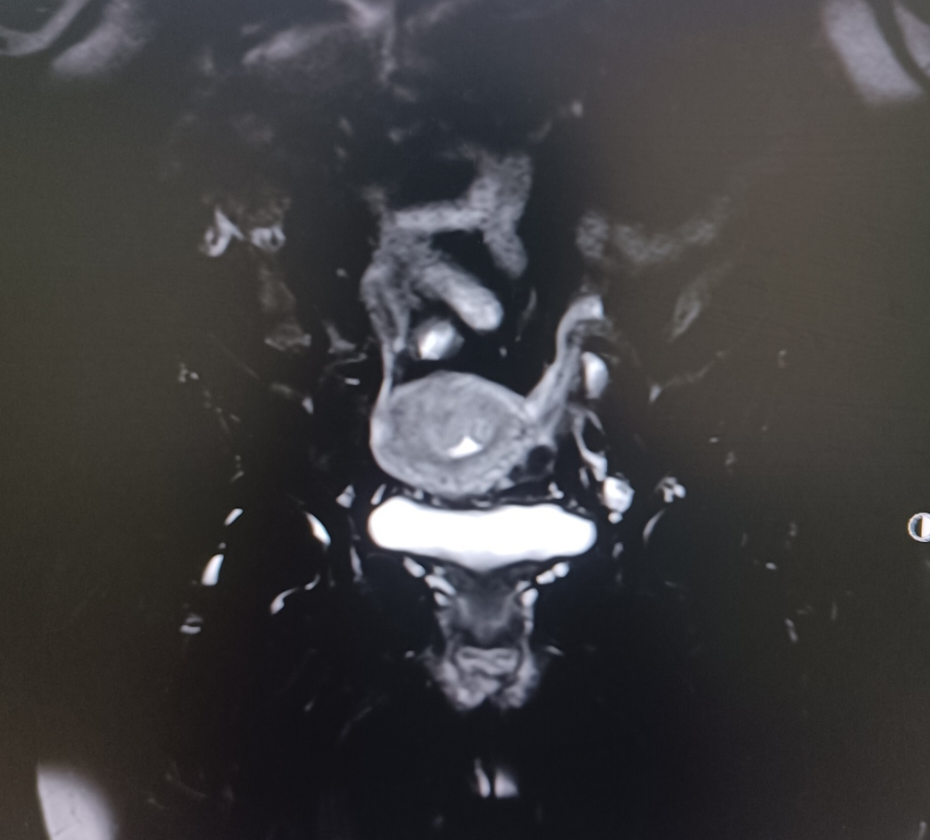

患者57岁,体重75千克,身高157厘米,血压147/100mmHg,绝经3年,阴道流血水样分泌物3个月,淋漓不尽,自服抗生素治疗无效就医。当地医院行妇科彩超检查发现子宫内膜厚约13毫米,宫内节育器位置正常,给予取环+诊断性刮宫,术后病理组织学检查报告提示:低分化癌,建议免疫组化标记明确类型。随就诊我院。

MRI:

术前诊断:子宫内膜癌(低分化)

术后诊断:子宫内膜样低分化腺癌(IIIC1)(微卫星稳定型)